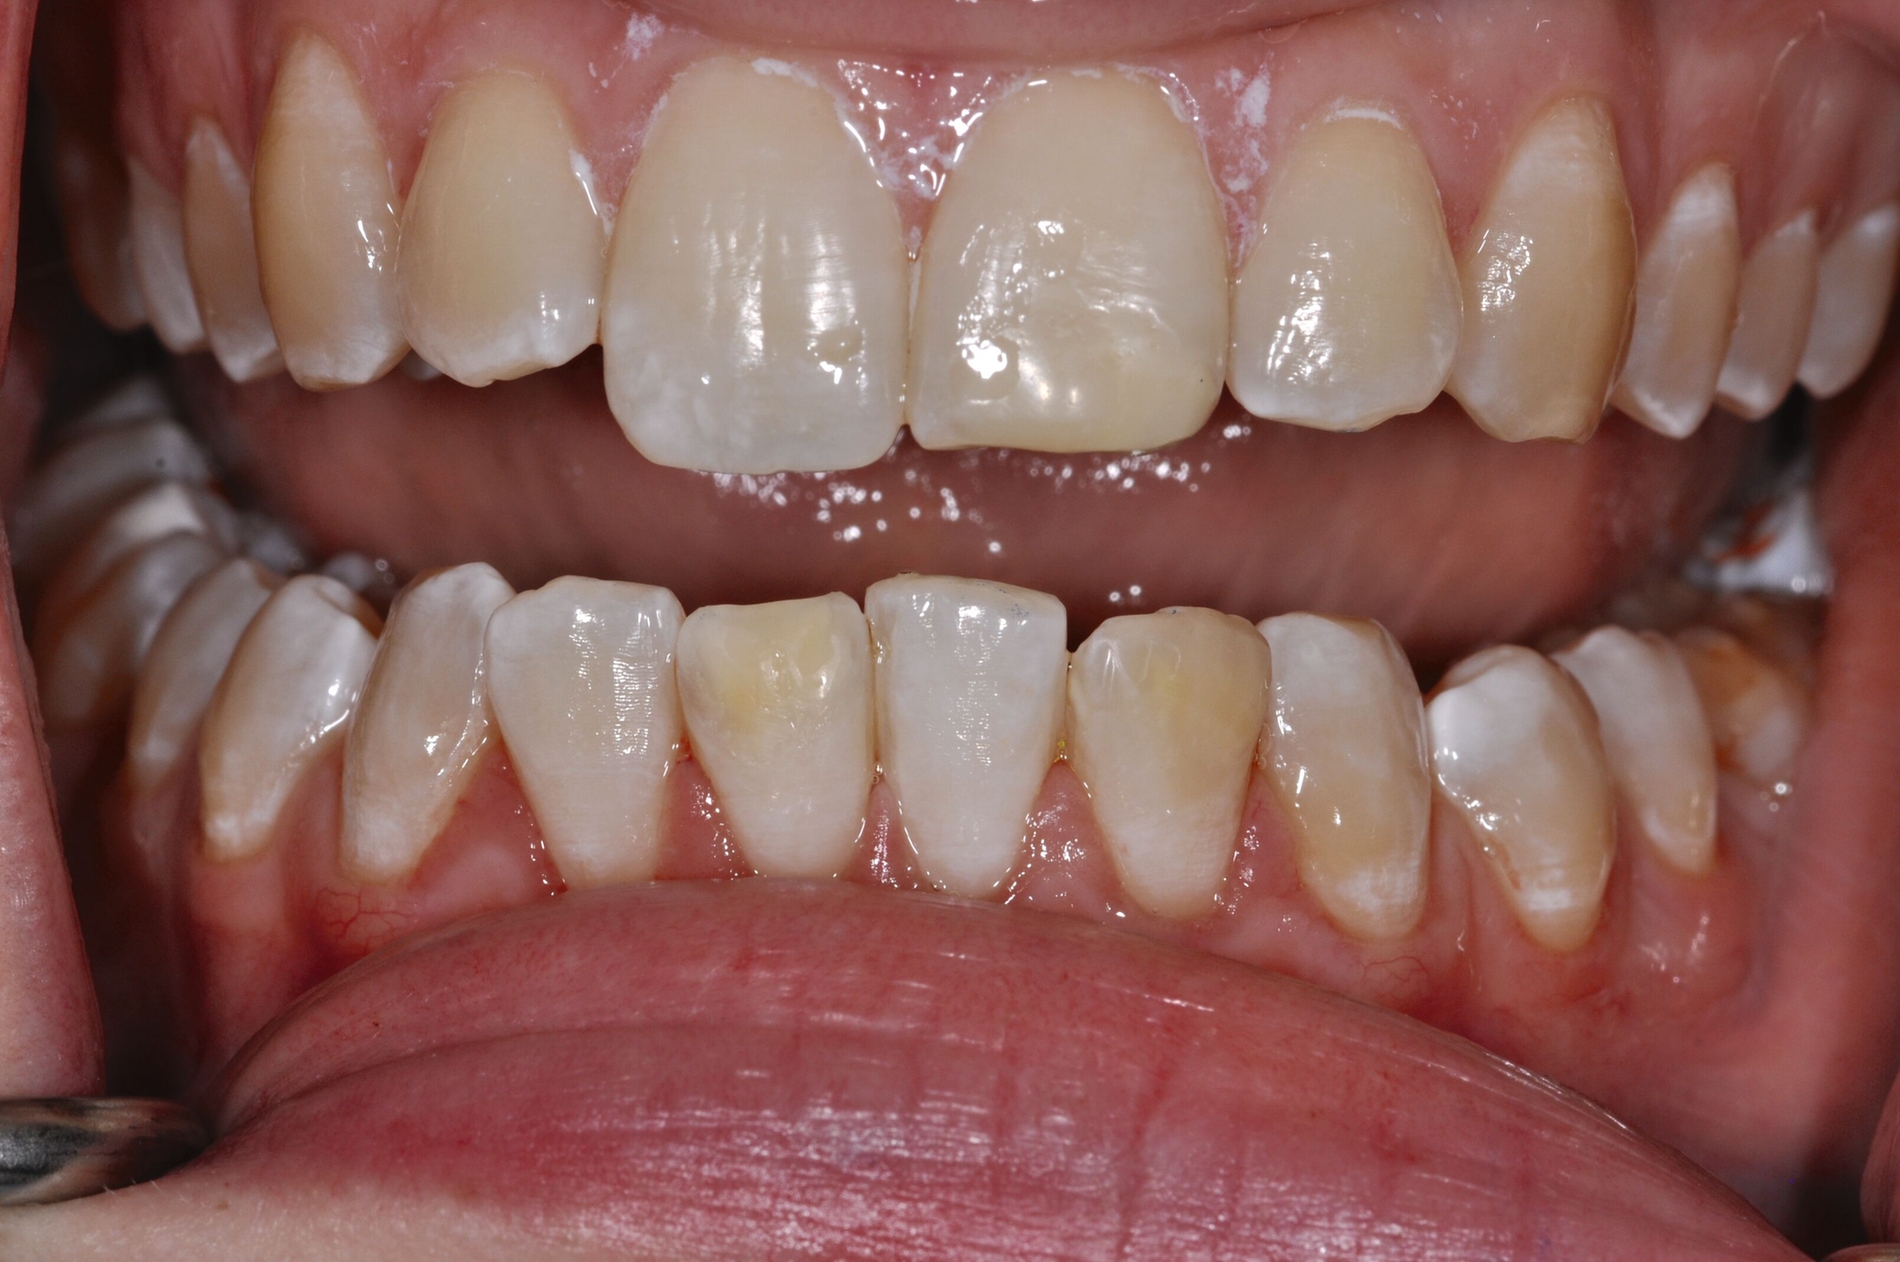

Die definitive Versorgung der MIH-affektierten Molaren und Frontzähne umfasst die adhäsive Versorgung direkt mit Komposit oder indirekt mit Keramik oder Komposit.

Die direkte Versorgung mit Komposit hat den Vorteil, dass durch die Verwendung von Dentinadhäsiven das Dentin dicht versiegelt werden kann. Hypersensitivitäten werden dadurch deutlich reduziert. Zudem kann der Zahn bei der direkten Versorgung sehr defektorientiert versorgt werden (Abbildung 7).

Die Versorgung der MIH-Frontzähne entspricht dem Vorgehen im Seitenzahnbereich. Problematisch ist die Maskierung der Opazitäten. Dazu müssen opake Komposite verwendet werden und es muss eine Schichtstärke von circa 1,5 mm garantiert sein (Abbildung 9).